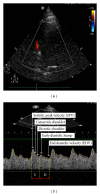

Ultrasound is a safe, portable, relatively inexpensive, and easily accessible imaging modality, making it a useful diagnostic and monitoring tool in medicine. Anesthesiologists encounter a variety of emergent situations and may benefit from the application of such a rapid and accurate diagnostic tool in their routine practice. This paper reviews current and potential applications of ultrasound in anesthesiology in order to encourage anesthesiologists to learn and use this useful tool as an adjunct to physical examination. Ultrasound-guided peripheral nerve blockade and vascular access represent the most popular ultrasound applications in anesthesiology. Ultrasound has recently started to substitute for CT scans and fluoroscopy in many pain treatment procedures. Although the application of airway ultrasound is still limited, it has a promising future. Lung ultrasound is a well-established field in point-of-care medicine, and it could have a great impact if utilized in our ORs, as it may help in rapid and accurate diagnosis in many emergent situations. Optic nerve sheath diameter (ONSD) measurement and transcranial color coded duplex (TCCD) are relatively new neuroimaging modalities, which assess intracranial pressure and cerebral blood flow. Gastric ultrasound can be used for assessment of gastric content and diagnosis of full stomach. Focused transthoracic (TTE) and transesophageal (TEE) echocardiography facilitate the assessment of left and right ventricular function, cardiac valve abnormalities, and volume status as well as guiding cardiac resuscitation. Thus, there are multiple potential areas where ultrasound can play a significant role in guiding otherwise blind and invasive interventions, diagnosing critical conditions, and assessing for possible anatomic variations that may lead to plan modification. We suggest that ultrasound training should be part of any anesthesiology training program curriculum.